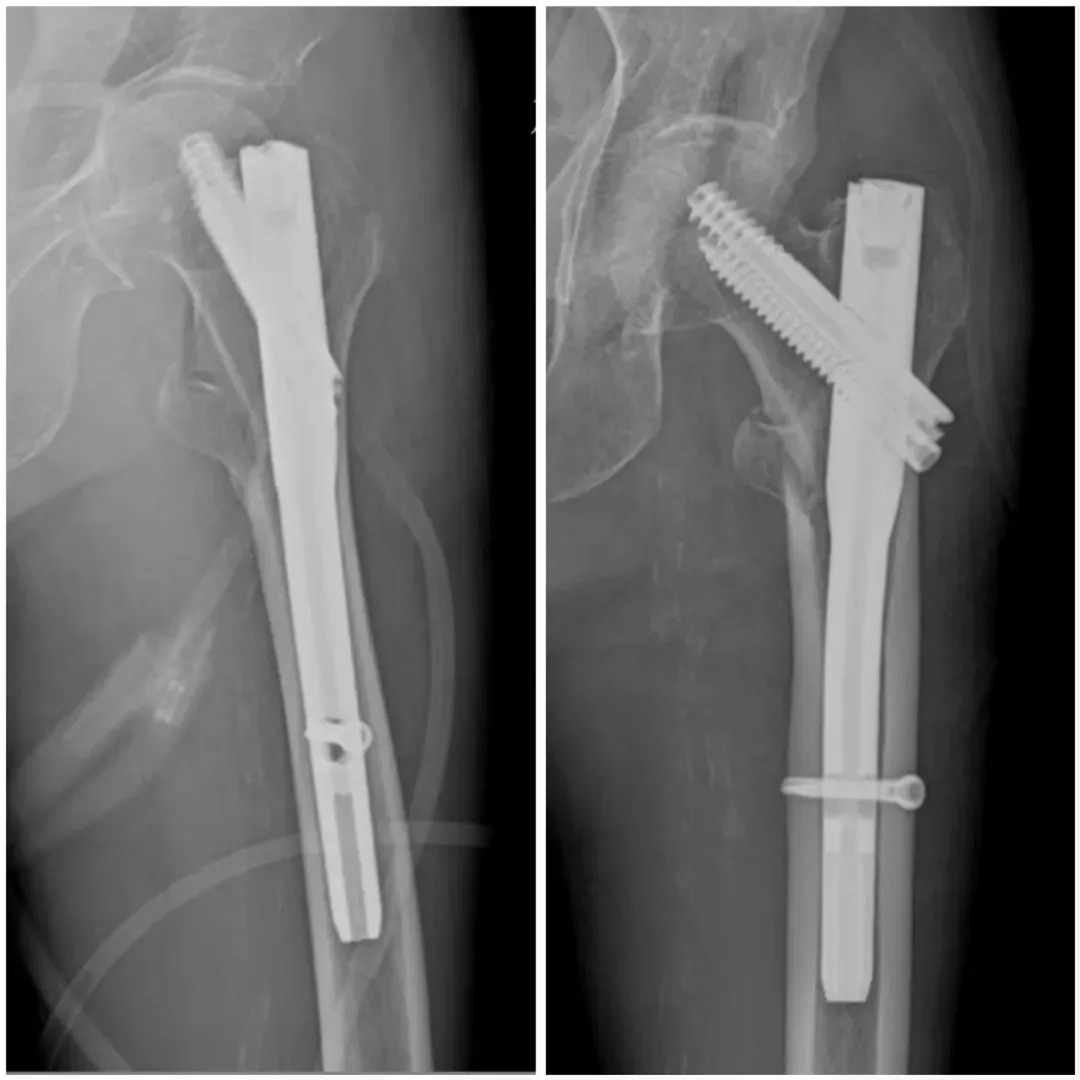

案例二

91歲的患者因“捧傷致左髖部疼痛伴活動受限4小時”入院。入院診斷為左股骨粗隆間骨折,伴有貧血、肺氣腫、帕金森病、阿爾茲海默病、泛發(fā)性帶狀皰疹、陳舊性腦梗死、胸8椎體陳舊性壓縮性骨折等多系統(tǒng)疾病。入院后,患者接受了全面的輔助檢查,并給予患肢抬高制動、止痛、補液、皮牽引等對癥治療。多學(xué)科團隊(MDT)進行了綜合評估和術(shù)前討論,決定在腰硬聯(lián)合麻醉下行左股骨粗隆間骨折閉合復(fù)位Intertan內(nèi)固定術(shù)。

術(shù)前

術(shù)后

術(shù)后,患者轉(zhuǎn)入重癥監(jiān)護室觀察2天,病情穩(wěn)定后轉(zhuǎn)入普通病房。在醫(yī)護人員的精心照料下,患者恢復(fù)良好,左髖部疼痛明顯減輕,活動能力逐步恢復(fù)。